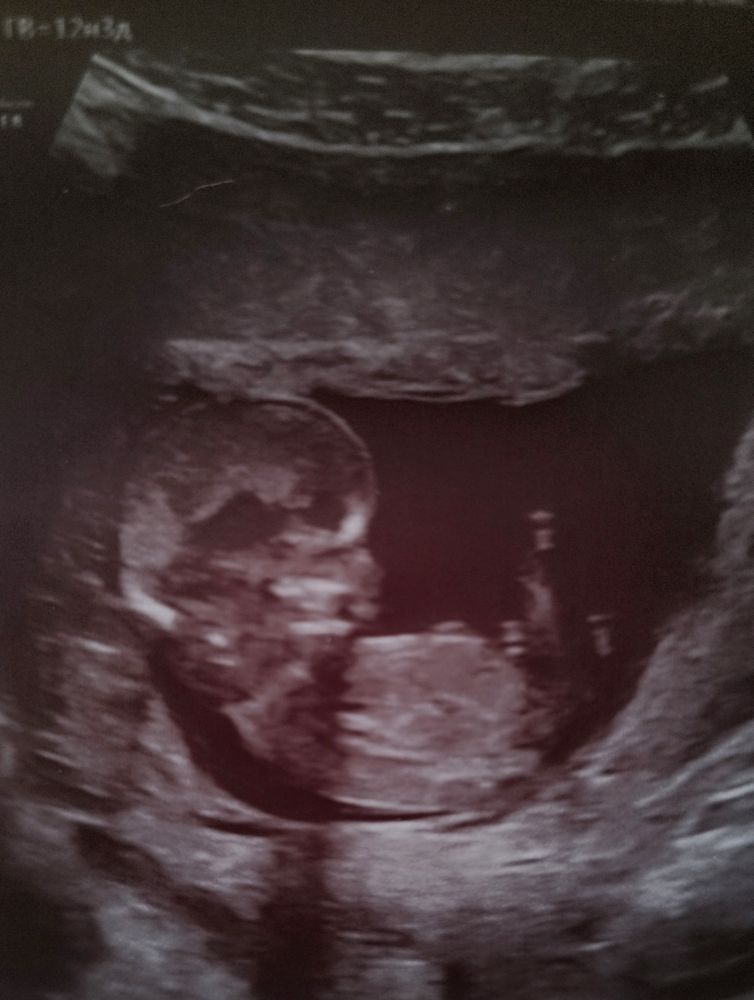

УЗИ, КТГ, доплерКто видит что-нибудь? Врач сказала, что малыш очень сильно крутился, прыгал, вертелся. Сложно было сделать даже один четкий снимок. Всё, что получилось. Срок по месячным 12 нед. 3 дня

Кто видит что-нибудь? Врач сказала, что малыш очень сильно крутился, прыгал, вертелся. Сложно было сделать даже один четкий снимок. Всё, что получилось. Срок по месячным 12 нед. 3 дня